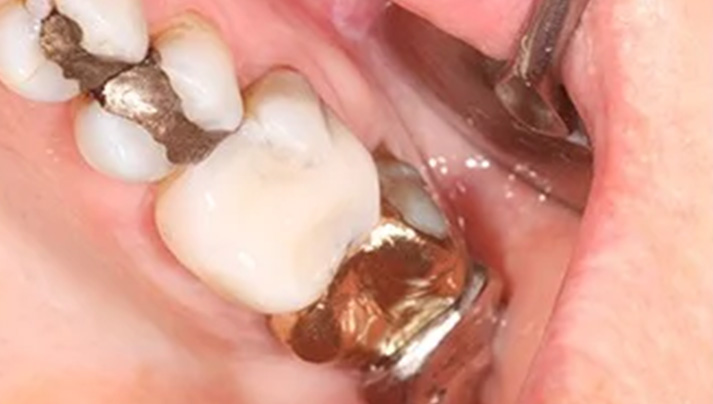

Before and Afters – White Fillings